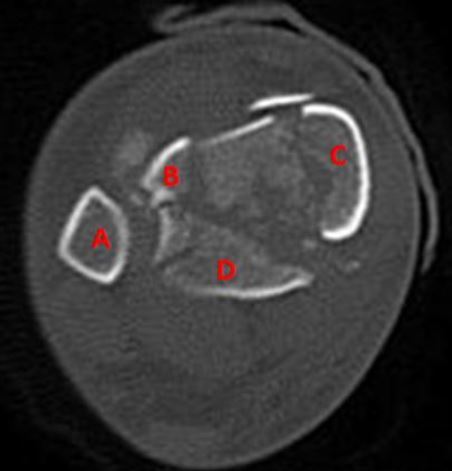

A 33-year-old male is involved in a motor vehicle accident and suffers a right pilon fracture. Which of the bone fragments labeled on the distal tibia in the axial CT scan shown in Figure A is attached to the posterior tibiofibular ligament?

Figure A is an axial CT scan slice of an intra-articular distal tibia fracture. The bands of the posterior tibiofibular ligament pass obliquely from the fibula to the posterolateral aspect of the distal tibia. The ligaments of the ankle often remain intact after a pilon fracture producing the major fracture segments consisting of posterolateral or Volkmann’s fragment (labeled D), the anterolateral or Chaput fragment (labeled B), and the medial fragment (labeled C).